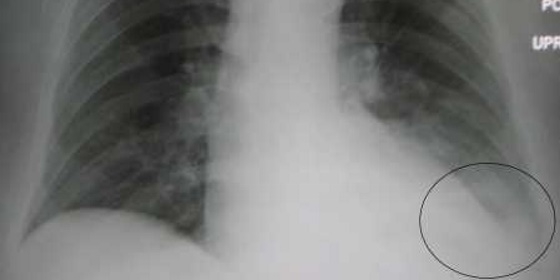

Portugal é o segundo país da Europa com a mais elevada taxa de mortalidade padronizada por pneumonia, colocando o país “mal na fotografia”, como reconheceu a diretora do Programa Nacional das Doenças Respiratórias.